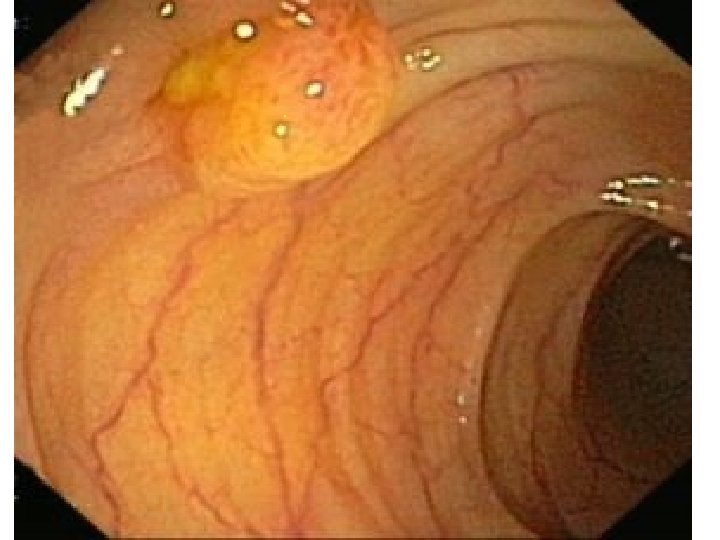

Adenokarcinom slinné žlázy

Adenom slinné žlázy